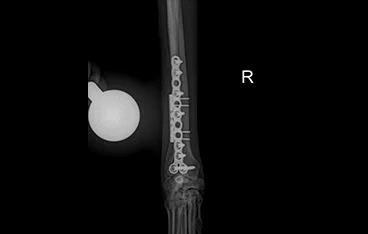

• PLATE 수술 전

PLATE 수술 후